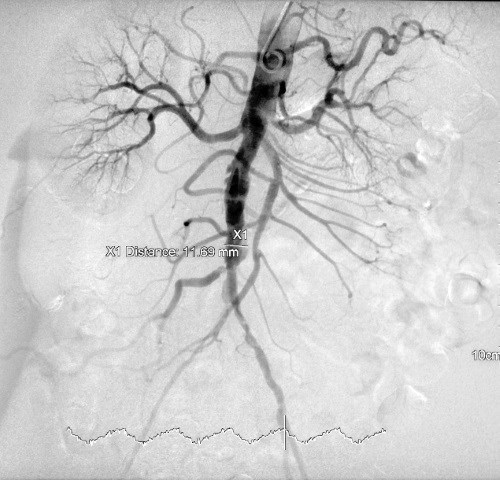

Кровеносные сосуды можно увидеть с помощью специального типа рентгеновских лучей. Такой снимок называют ангиограммой.